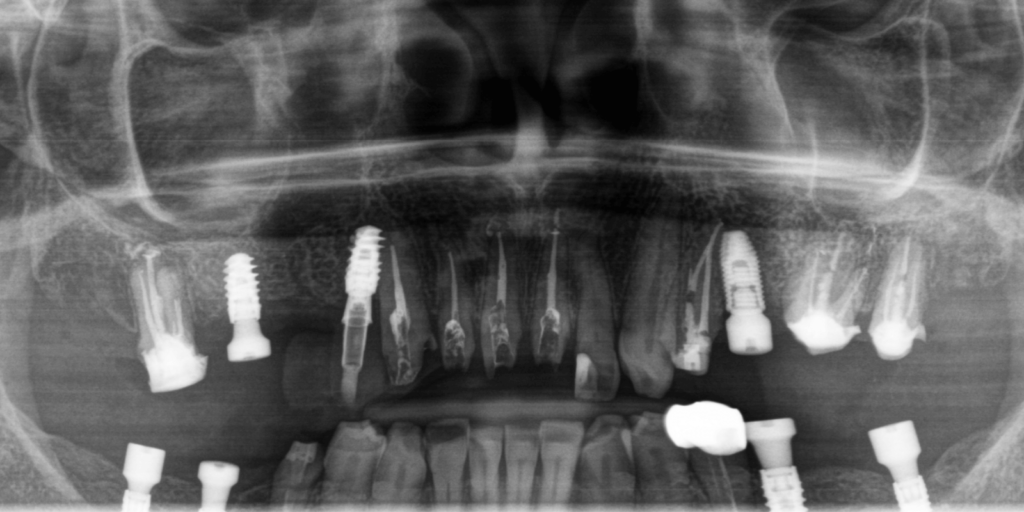

На верхней челюсти снять мостовидные протезы и удалить 4 зуба. Выполнить повторное лечение корневых каналов ("реэндо"). Также установить импланты Straumann BLX.

Во фронтальном участке улыбки, на зубах 21-13 снять одиночные коронки и одноэтапно провести эндодонтическое лечение. Работу по протезированию выполнить путем перенесения mock-up модели.

Нижняя челюсть

Верхняя челюсть